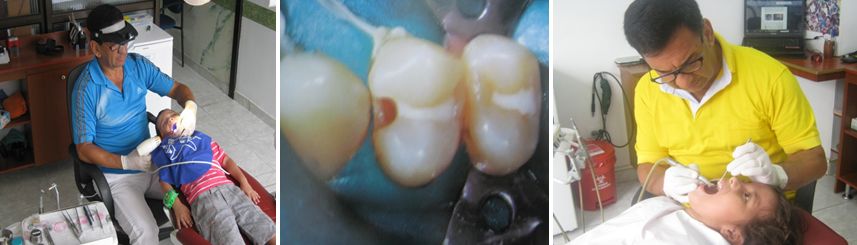

- TERAPEUTICA PULPAR EN DENTICION TEMPORAL

caries dental y el trauma favorecen la infección y daño del tejido pulpar de los dientes deciduos. Los tratamientos de endodoncia en esta dentición contribuyen a mantener los elementos dentales comprometidos en forma adecuada hasta la época normal del recambio.

Los tratamientos de endodoncia son procedimientos de práctica exclusiva del Odontólogo Pediatra. Se requiere de gran conocimeinto científico y de un manejo instrumental refinado que permita el éxito en los procedimientos.